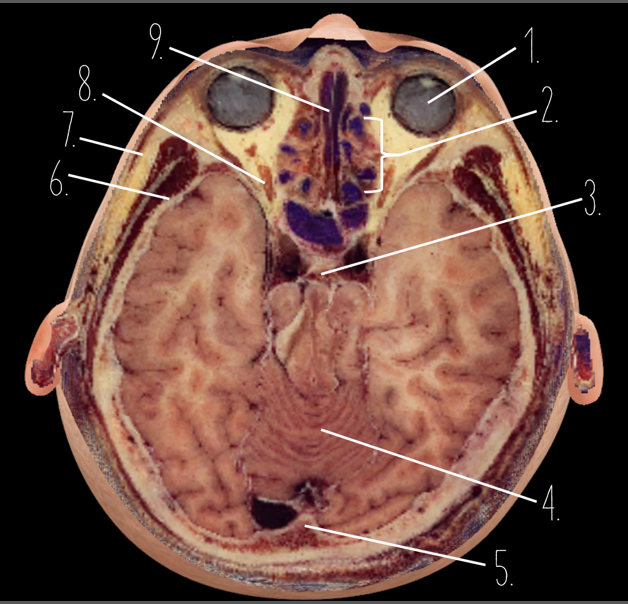

1?

Globe of Eye

2?

Ethmoid Sinus

3?

Pituitary Gland

4?

Cerebellum

5?

Internal Occipital Protuberance

6?

Wing of Sphenoid

7?

Zygomatic Arch

8?

Optic Nerve

9?

Vomer